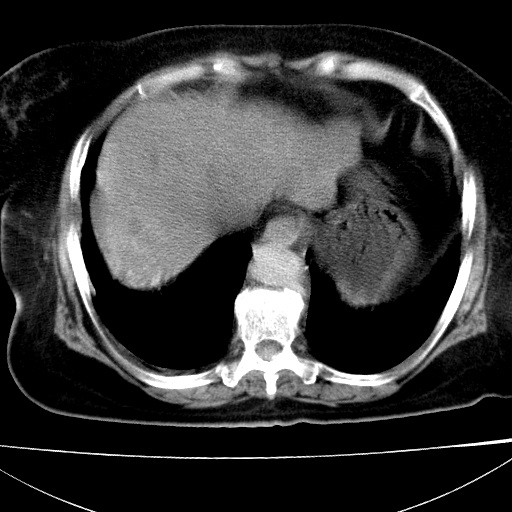

患者女74岁;右上腹胀痛1月,伴恶心,无发热;生活在疫水区。有术后病理及术后半年的追踪ct.

1)慢性血吸虫病(典型)。2)肝硬化。3)肝癌?4)胆囊炎。5)少量腹水。6)右侧少量胸腔积液。

支持.边缘见高密度线条样钙化影.

肝脏体积缩小,肝裂增宽,边缘不平呈波浪状,肝右叶见分隔状条索形钙化,亦见多结节低密度灶,边界不清,肝周可见少许液性暗区,胆囊增大内密度均匀,脾脏下缘低于脏脏的下缘,胸腔亦见液性暗区,余未见明显异常.

诊断:1肝硬化并慢性吸血虫病,脾肿大

2肝内占位,考虑肝癌可能性大,建议做增强

3胆囊炎, 4少量腹水及胸水

胆囊增大饱满,壁增厚。胆囊颈部见软组织密度影。临近肝右叶前段见片状低密度区,病灶下部见条状钙化,少量胸腹腔积液。意见:胆囊颈癌累及肝脏。

病人以胆囊癌手术的,病理结果为中分化腺癌。

现在看看肝右叶内圆形低密度影你们考虑什么呢?

肝内圆形低密度影考虑扩张的胆管

请看3mm重建像如下: